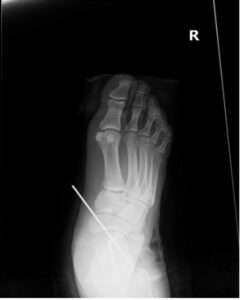

Subtalar Dislocation. Post-surgical reduction AP. JETem 2024

Subtalar Dislocation. Post surgical reduction AP. JETem 2024